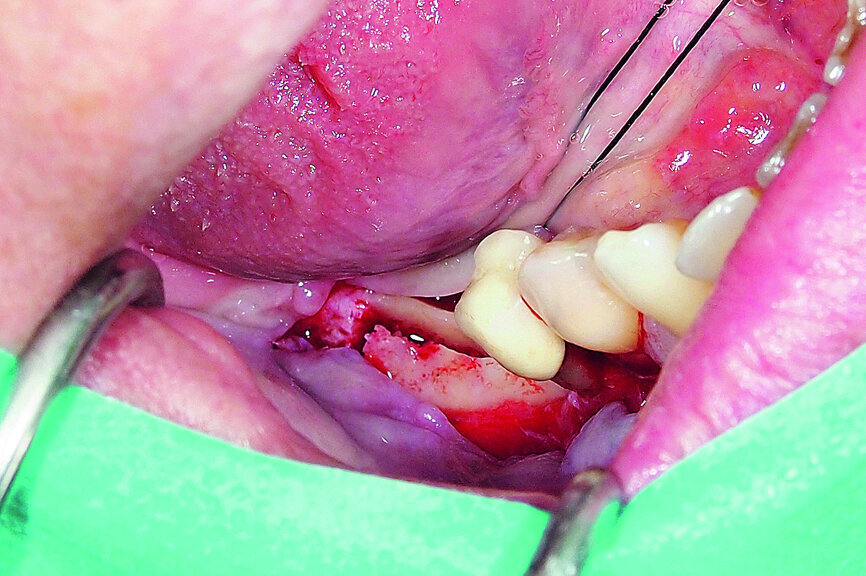

Fig. 15: Combination of full- and partial-thickness flap elevation.

A demonstration of this technique is shown in Figures 13 to 20. This case presents an elderly woman who had lost her teeth in the lateral mandible decades ago. Being a healthy non-smoker with good oral hygiene, no history of periodontal disease and low masticatory forces, she was an adequate candidate for bone grafting together with implant placement. The future restorative margins allowed the usage of ridge splitting (Figs. 13 & 14). Therefore, we opted for a ridge split with vertical releases carried out utilising a partial-thickness flap. The periosteum was left attached in order not to impede the perfusion of the buccal plate (Fig. 15). After ridge splitting, the buccal and lingual plates were separated with the use of bone spreaders (Split-Control Plus, Meisinger) to allow the placement of two GC Aadva Standard implants, one of 3.3 mm in diameter and 8.0 mm in length and the other measuring 4.0 mm in diameter and 8.0 mm in length (Figs. 16–18).